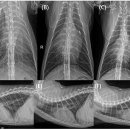

“심장질환·내과 특화진료로 학술적 성장” 진료 케이스 연구논문 발표 및 세미나 진행…임상 데이터 바탕으로 학술 가치 높여가 ​ ​ ​ 한남심장내과동물병원은 김병준 원장이 지난 10여년 간의 임상 경험과 미국 및 유럽대학 연수를 통해 쌓은 심장질환 진단과 치료 전문성을 바탕으로 개원한 심장 내과 전문병원이다...

산소포화도가 많이 낮지 않아서 산소를 쐬지 않고 검사를 진행했어요 ​ ​ 심장초음파를 보면서 설명해 주시는 원장님 ​ ​ 저번에 방문해서 처방 받았던 약을 먹고...물도 떠 주셨어요👍🏻 패드는 실수를 할까봐 저희가 깔았답니다! ​ 진심동물내과심장병원 대구광역시 수성구 동대구로 346 서한포레스트 상가동 1층(대로변에서...